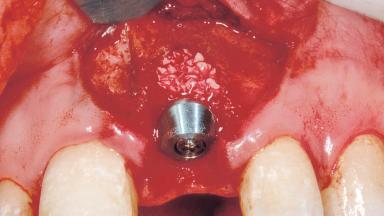

Immediate Placement of an Implant in a Maxillary Left Central Incisor Site

A 33-year-old female patient presented with an upper left central incisor that required extraction after a failed endodontic therapy. The tooth had been traumatized when the patient was a teenager and had undergone several endodontic treatments, including two apicectomy procedures. The patient was in good health and did not smoke. Clinical examination showed that the patient had a high lip line. In full smile, the gingival margins of the upper teeth were visible to the first molars. The gingival margins of central incisors 11 and 21 were only just showing. Examination of tooth 21 confirmed that the tooth was mobile and had hypererupted by 1 mm.